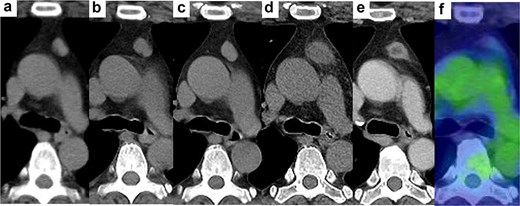

In the year X, a woman in her forties presented for the evaluation of a 2.8-cm AMN (Fig. 1d). She was a former smoker and was on medication for diabetes mellitus and hyperlipidaemia. In X-4, her physician performed computed tomography (CT) scan to exclude malignancy for uncontrolled diabetes mellitus and detected a well-circumscribed and slightly lobulated 1.4-cm AMN (Fig. 1a). Upon follow-up, the AMN had grown to 1.7 cm and 2.3 cm in X-2 (Fig. 1b) and X-1 (Fig. 1c), respectively. The AMN on CT at referral was enlarged but had blurred margins and low density. On enhanced CT performed 2 months later, the size of the AMN was 1.4 cm with a low density in the central area (Fig. 1e). 18F-fluorodeoxyglucose positron emission tomography (FDG-PET) performed 3 months later showed the AMN measured 1.2 cm with little accumulation (Fig. 1f). FDG-PET and brain MRI revealed no metastases. There were no abnormal values for any of the laboratory tests, including tumour markers, anti-acetylcholine receptor antibody and thyroid function. We considered this change to suggest that the TM regressed spontaneously with an unclear aetiology and proposed close observation as one possible option. However, the patient opted for resection and pathological examination. Six months after referral, we performed a thoracoscopic resection of the AMN with a sufficient surgical margin. The target nodule was detected in the resected specimen. The peri- and post-operative courses were uneventful. The patient was discharged on post-operative day 6.

Changes in AMN on CT. (a) 4 years before visiting our hospital, (b) 2 years before, (c) 1 year before, (d) at the time of visiting our hospital, half a year after the removal of all dental crowns, (e) 2 months after visiting our hospital, (f) positron emission tomography 3 months after visiting our hospital.